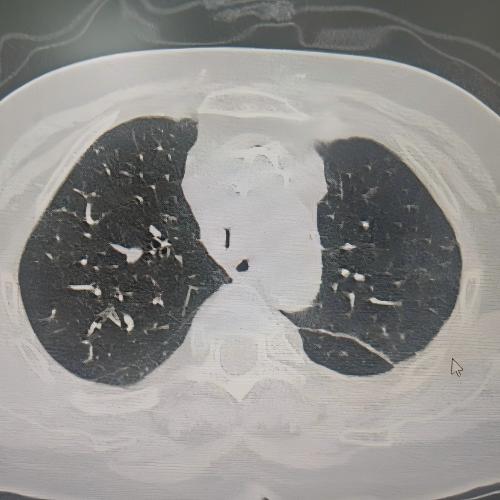

患者为75岁女性,因“反复咳嗽咳痰、气促10余年,加重3月”,于3月3日入住湘雅三医院呼吸与危重症医学科。入院时患者呼吸困难症状严重,CT检查提示气道存在严重狭窄,随时面临窒息风险。经管床医生杨红辉评估,患者气管狭窄情况复杂:最狭窄处管腔直径仅剩1-3mm,科室最细的4.0mm支气管镜也无法通过;狭窄位置极低,下缘距隆突仅1.6cm,意味着无法通过气管切开绕过病灶;狭窄处周围组织的CT值高达60-70Hu且无强化,因而直接植入支架存在无法撑开或加重堵塞的风险;同时,患者无法耐受全身麻醉,仅能采用利多卡因进行表面麻醉,操作难度较大。

方案确定后,ICU团队何智辉、邢伟、邓龙天为患者建立体外生命通道;呼吸介入团队孟婕、杨红辉、刘建明、邹丽君、贺一峻等通过球囊对狭窄部位进行预扩张,随后在距隆突仅1.6cm的低位气道精准植入支架。支架贴合良好,气道顺利开通,全程操作约1.5小时。患者当晚撤离ECMO,次日从ICU转回普通病房。后续肺泡灌洗液检测显示,患者大气道狭窄的原因为气管结核导致的瘢痕性狭窄。